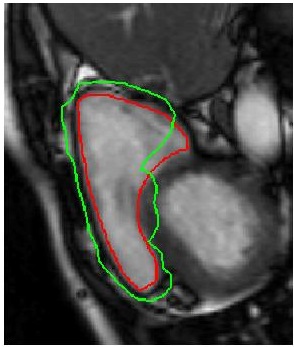

Table 2 summarizes the performance of different methods, and Figure 3 shows superimposed manual contour of the RV (red) and the deformed contour of the registered image (green). Better registration is reflected by closer alignment of the two contours. Once again it is obvious that has the best performance amongst all competing methods, and its advantages over when including deformation consistency.

![]() |

| (a) | (b) | (c) | (d) |